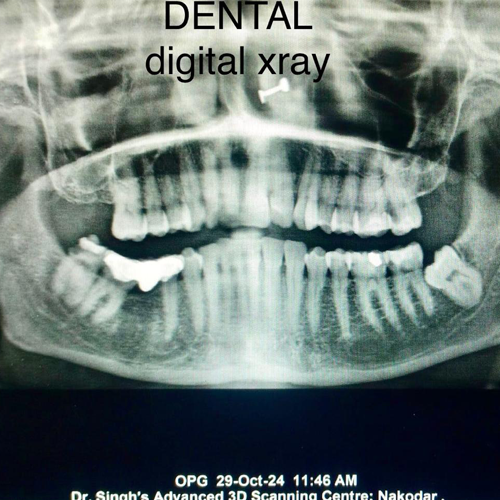

Best Scanning Center In Nakodar